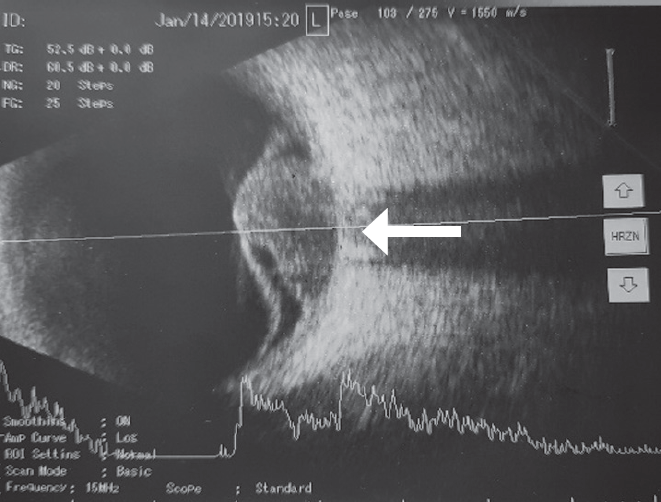

Ophthalmological examination data included examination of the visual acuity of the right eye of 0.8, which was incorrigible and that of the left eye was hand motion. The tonometry result was 18/17 mmHg. Biomicroscopy revealed no abnormalities in the anterior segment of both eyes. Particular attention was paid to the search for Lisch nodules in the iris, which were absent. At ophthalmoscopy, no focal pathologic change was detected in the right eye, while there was a protruding multinodular pink–orange neoplasm in the optic nerve head of the left eye, with clear boundaries, at the base of which, a retinal detachment was visualized in the lower fundus segments (Fig. 2). At the B-scan ultrasound examination, the optic nerve head had a protruding fungiform neoplasm (with height of up to 6.7 mm and diameter of up to 13.0 mm), medium echogenicity, and inhomogeneous density, at the base of which, retinal detachment was observed in the lower fundus segments (Fig. 3). Magnetic resonance imaging of the orbits also confirmed the presence of left eye neoplasm (Fig. 4).

Fig. 3. B-scan ultrasound of left eye. Tumor grows from optic nerve (white arrow) causing secondary retinal detachment

Рис. 3. Ультразвуковое В-сканирование левого глаза. Опухоль располагается непосредственно над зрительным нервом (белая стрелка), вызывая вторичную отслойку сетчатки